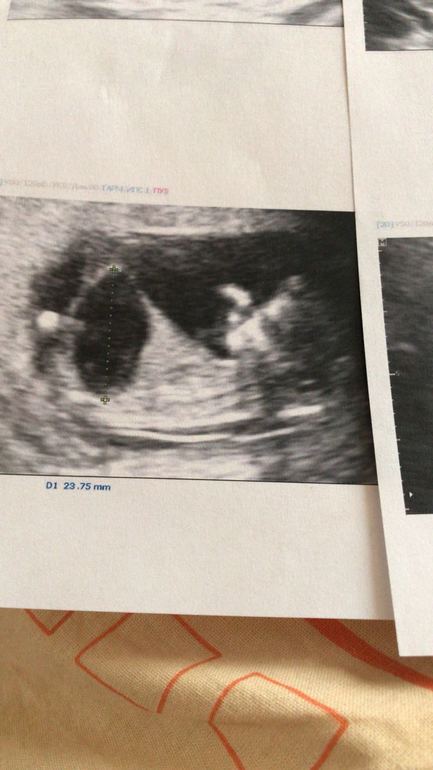

Шло время, я записалась на первый скрининг.. На сроке 11 недель и 3 дня я посетила врача. Когда поднесли датчик к животу, я сразу поняла, что что-то не так. Животик моего малыша была размером больше чем его голова... 30 минут длилось узи, все было как в тумане.. Широкое ТВП, диагноз предположительно мегацистис.. И тут началось, узи, узи4D, узи экспертного класса, меня осматривали доктора и кандидаты медицинских наук.. Все твердили в один голос "Аборт".

На сроке почти 14 недель, в день аборта, на последнем узи было видно, что животик ребенка надулся мочой уже настолько, что сдавил сердечко... 13 марта все закончилось.